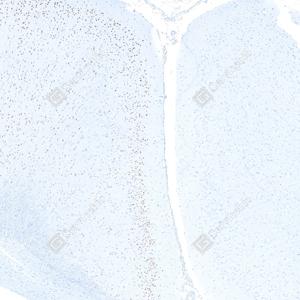

| IHC检测c-Fos蛋白(货号 GB15069). 样品: 大鼠脑, 4%多聚甲醛 (货号G1101) 固定12-24小时. 抗原修复: Tris-EDTA抗原修复液(pH 9.0) (G1203), 98℃, 20分钟. —抗: 1: 1000稀释, 4℃ 孵育过夜. 二抗: S-vision免疫组化多聚二抗(山羊抗兔),即用型 (货号G1302), 室温孵育20分钟. |